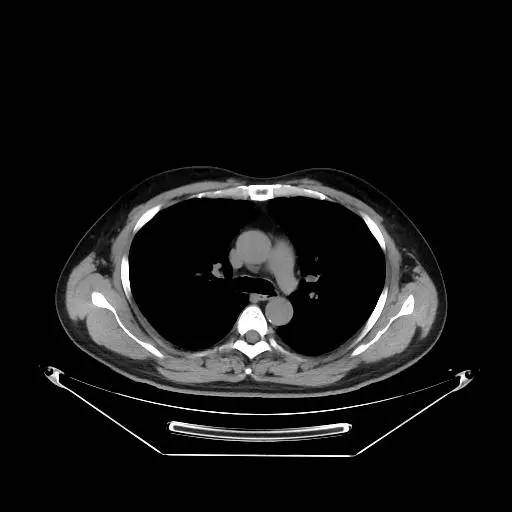

男,47岁,查体发现右肺小结节8月余。

[影像描述]

右肺上叶可见直径约7mm磨玻璃样结节,其内见空泡影,有浅分叶及血管集束征象,增强扫描无强化,余肺、纵隔未见明显异常。

右肺上叶不典型腺瘤样增生(AAH)

AAH的影像学特点为呈类圆形小病灶,边界清楚,淡至中等密度均匀的毛玻璃或磨砂玻璃阴影,不遮蔽其下的肺实质,多数在5 mm以下。